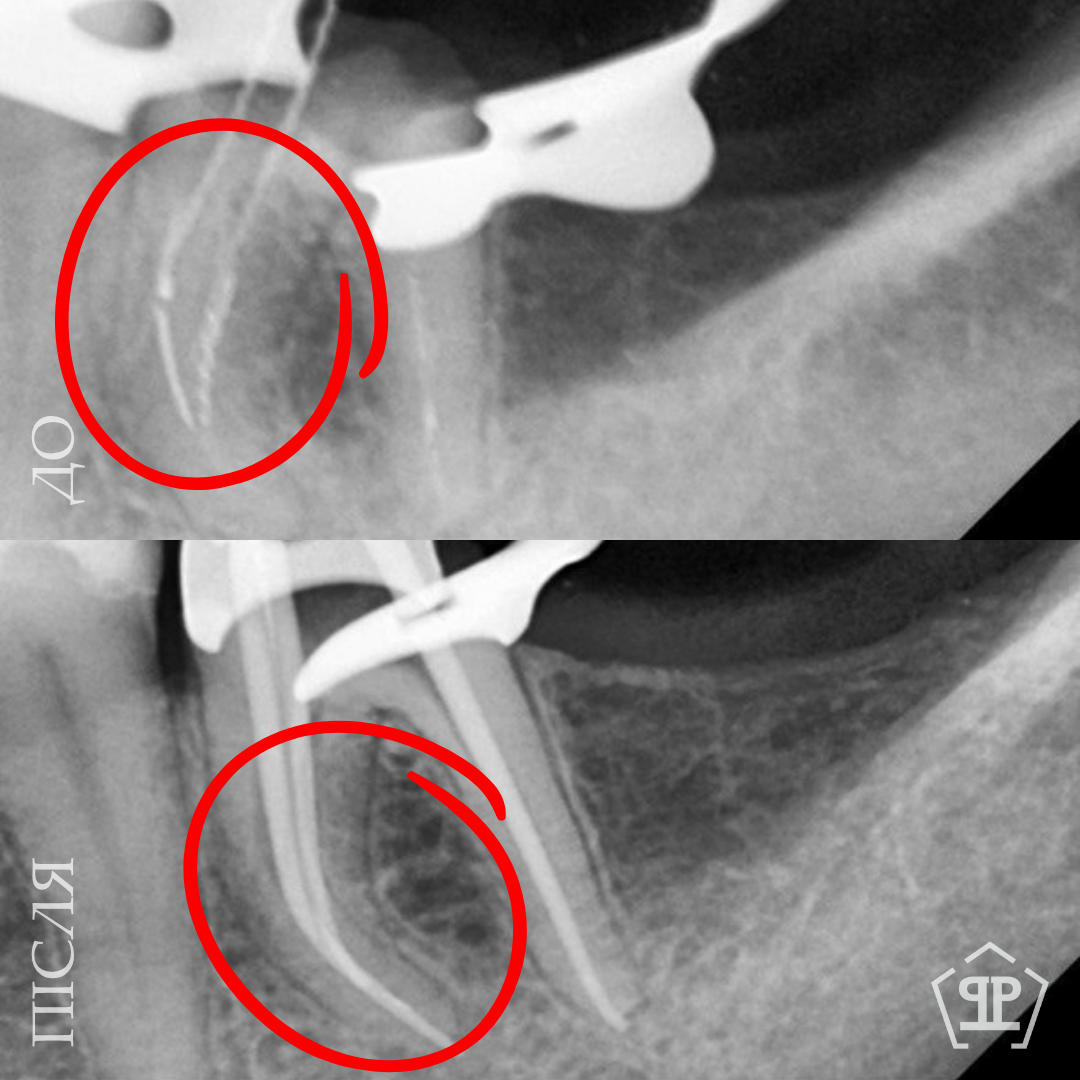

Перелечивание с удалением двух переломанных инструментов. Пациент обратился с осложнением предварительного эндодонтического лечения. В каналах были обнаружены два переломанных инструмента. Выполнены их удаление и пломбирование каналов с соблюдением современных эндодонтических протоколов.